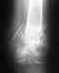

Добрый день!5 мес. назад получил травму правого локтевого сустава(вывих руки назад и вверх).Трещин и переломов нет.Ежедневными усилиями и ЛФК добился на сгибание 92 градуса на разгибание 155 градусов,а дальше не идет.Хотел Вашего совета ,делать операцию или поработать еще.Буду признательно благодарен за консультацию.Игорь,г.Каменец-Подольский.

• Кликните для загрузки файла Изображение 014.jpg